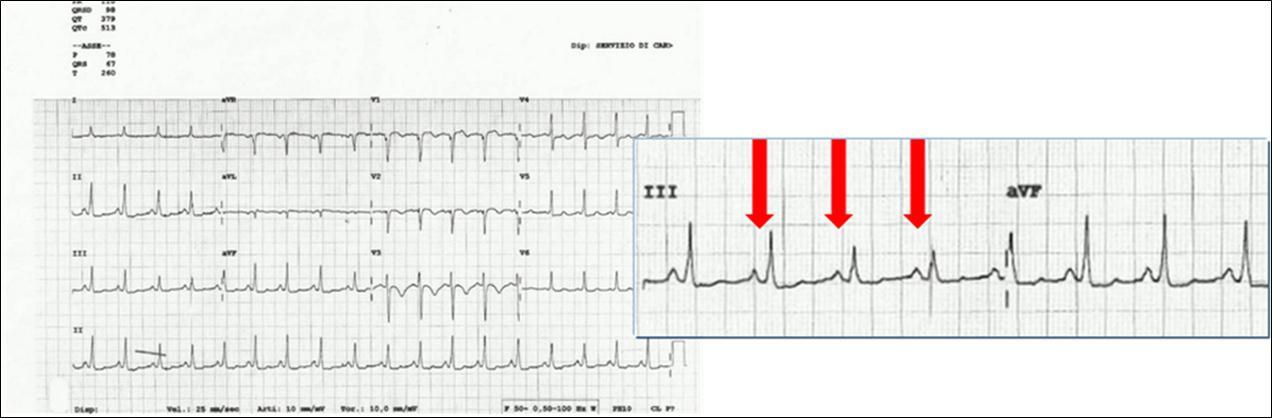

Rest electrocardiogram showed sinus tachycardia 110/m and no other anomalies. Nevertheless an ECG performed in the operatory room next day showed sinus tachycardia and a ventricular pre excitation compatible with a right anterolateral accessory pathway (Figure 1). The transthoracic echocardiogram performed in the same day demonstrated only left ventricle posterior apex, inferior and lateral wall mild thickening; furthermore, it showed two layered structure with numerous prominent trabeculae and deep intertrabecular recesses directly communicating filled with left ventricular cavity as assessed by Color Doppler. The ratio between tick non compacted layer and thin compacted part measured at end systole in short axis was > 2, according Jenni criteria for isolated left ventricular non compaction (ILVNC) (Figure 2) 1,2.

Figure 1.Sinus tachycardia and ventricular pre excitation